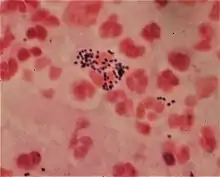

Gram negative Neisseria gonorrhoeae and pus cells

Gram-negative bacteria generally possess a thin layer of peptidoglycan between two membranes (diderm).[23] Lipopolysaccharide (LPS) is the most abundant antigen on the cell surface of most gram-negative bacteria, contributing up to 80% of the outer membrane of E. coli and Salmonella.[24] Most bacterial phyla are gram-negative, including the cyanobacteria, green sulfur bacteria, and most Pseudomonadota (exceptions being some members of the Rickettsiales and the insect-endosymbionts of the Enterobacteriales).[7][19]